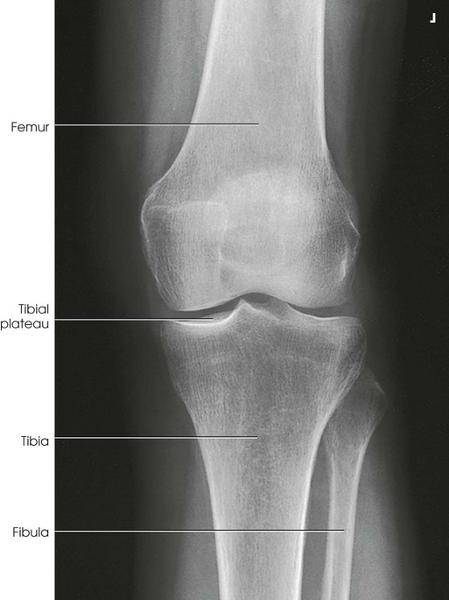

Structures Shown

• Both knees on one

exposure

• *May reveal a narrowing of the joint spaces which may

appear normal without weightbearing - especially on arthritic patients*

AP of the knee, Weightbearing